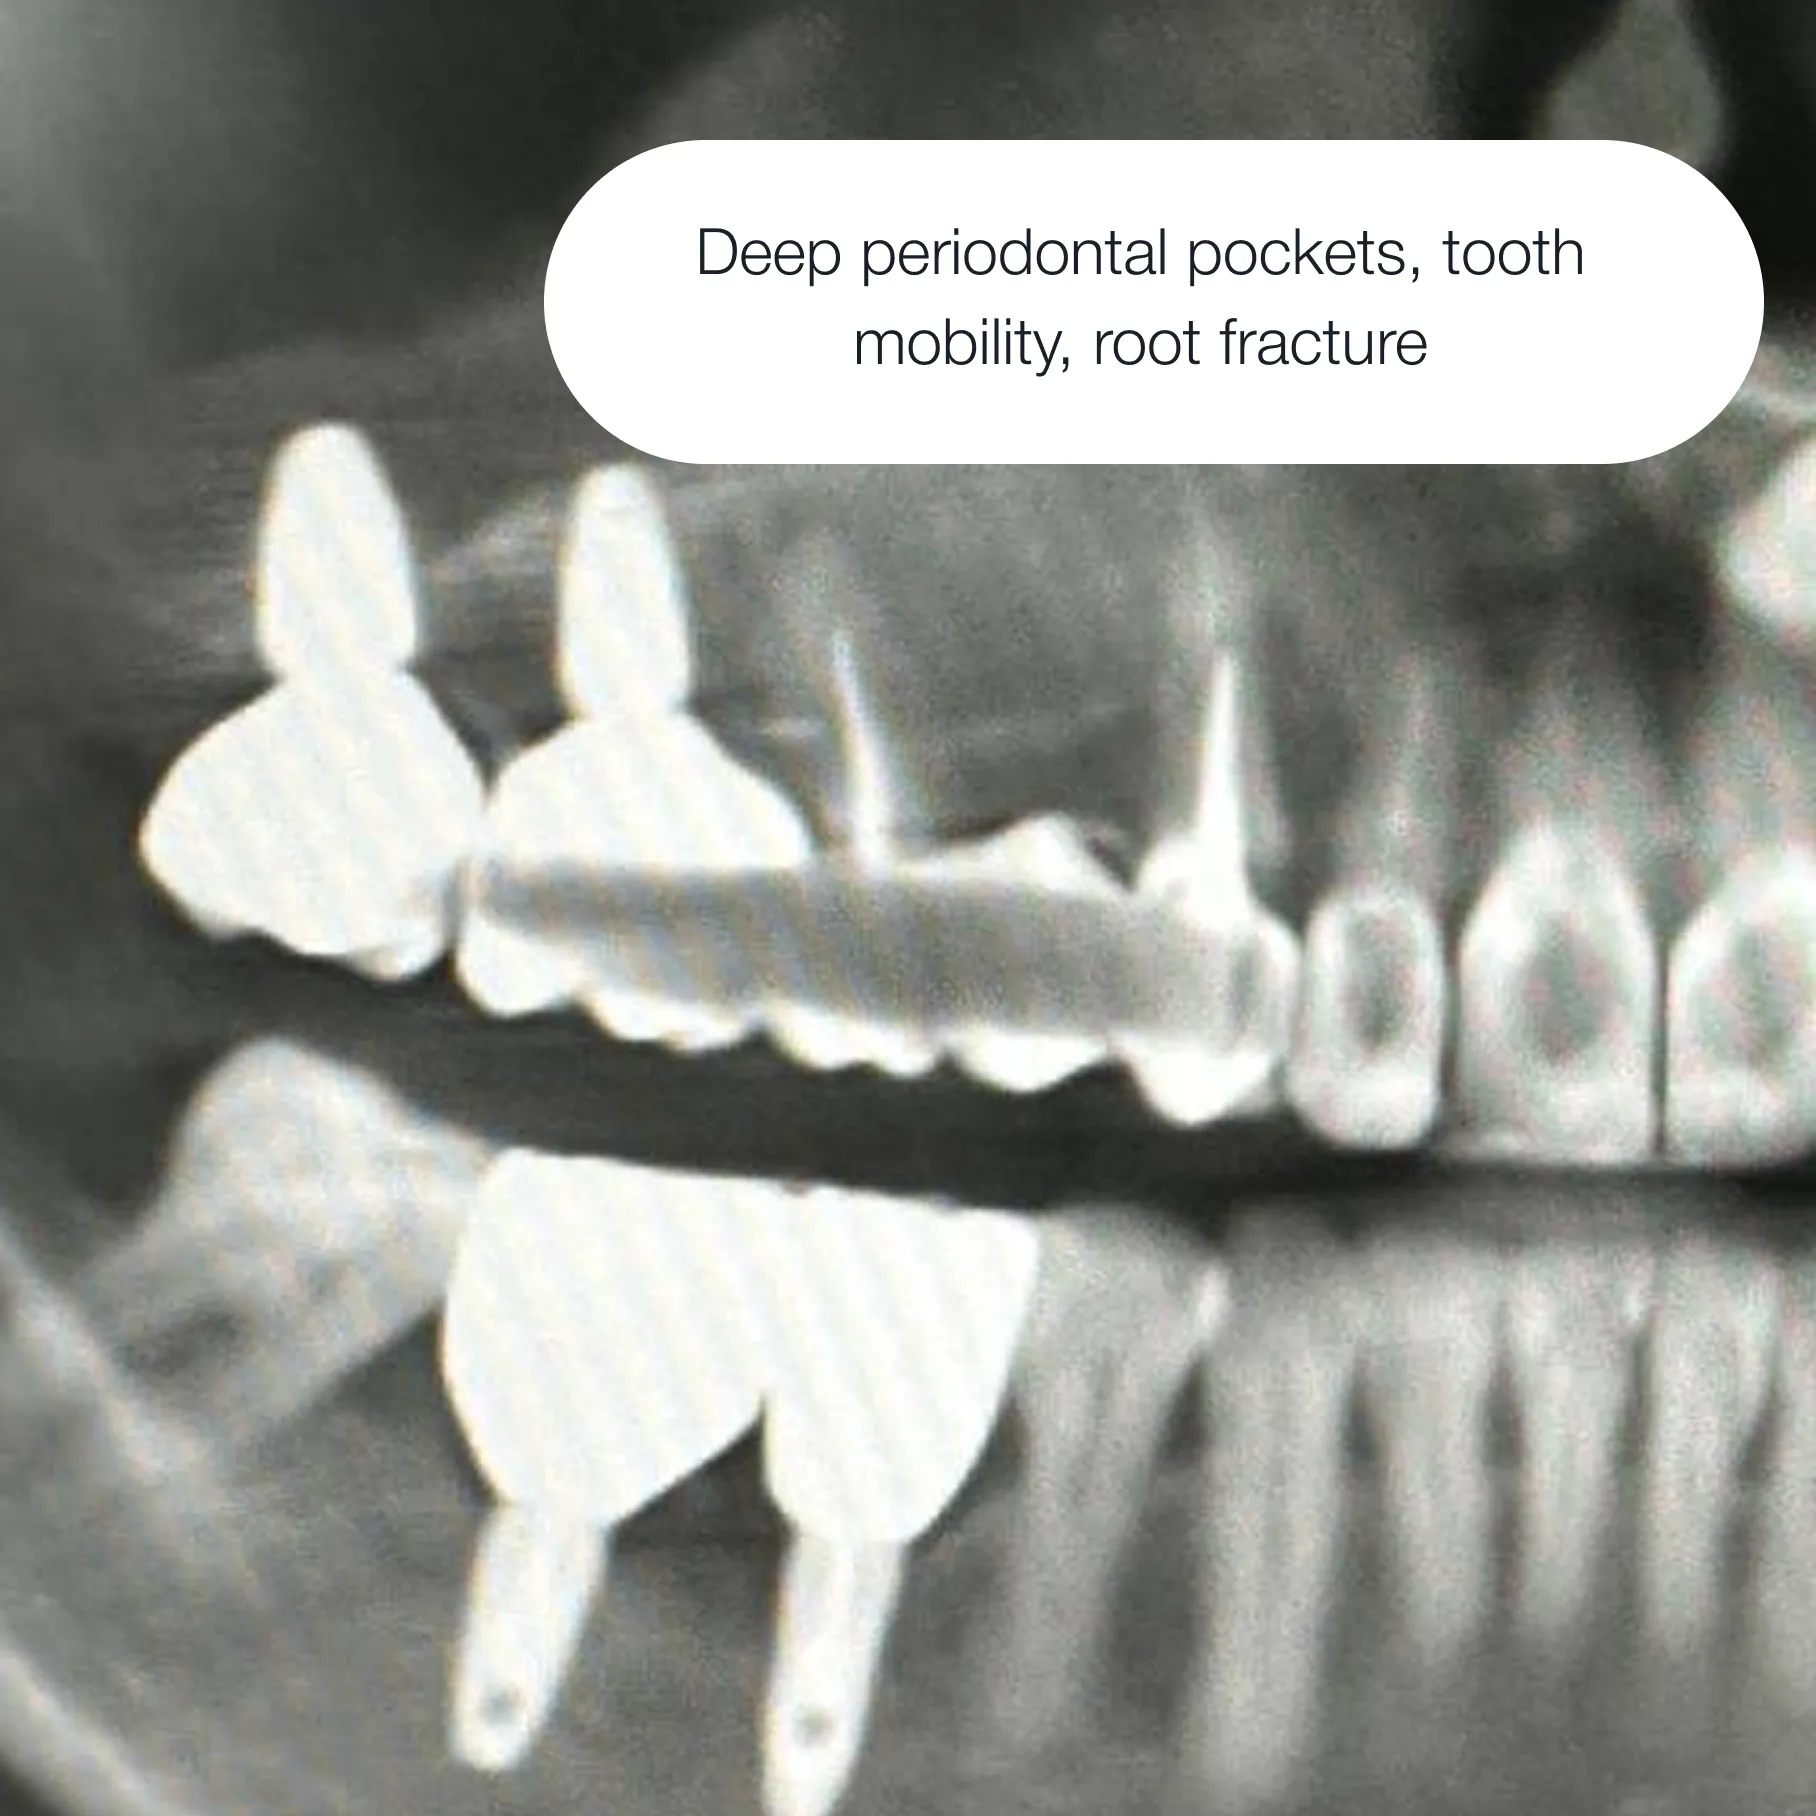

In most cases — yes.If the bone or gum tissue requires preparation, we perform bone grafting or soft tissue grafting to create optimal conditions for successful implant placement.

We restore bone volume using advanced techniques — tailored to your individual case.

This creates a strong, stable foundation for the implant, ensuring long-term integration and reliable performance for years to come.